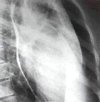

Рентгенография сердца с контрастированием пищевода – дистанционный лучевой метод исследования сердца, позволяющий определять положение, размеры, форму органа и отходящих от него крупных сосудов. С целью максимально точного определения границ сердца рентгенография выполняется в прямой, боковой, при необходимости – косых проекциях после приема пациентом контрастной бариевой взвеси. С помощью рентгенографии диагностируются некоторые виды пороков сердца, аневризма аорты и др. кардиопатология. Несмотря на доступность и физиологичность метода, он имеет определенный диагностический предел, в связи с чем всегда дополняется другими инструментальными исследованиями. В стоимость входит бариевый контраст.